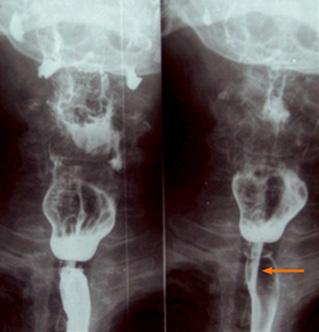

Figura 10. A. Anatomía normal con triangulo de Killian B. diverticulo de Zenker de Plummer Vinson (síndrome de Patterson Kelly) años)

Figura 11. Esofagograma. Presencia de membrana a nivel del esófago cervical que solo permite un paso filiforme de contraste (flecha)